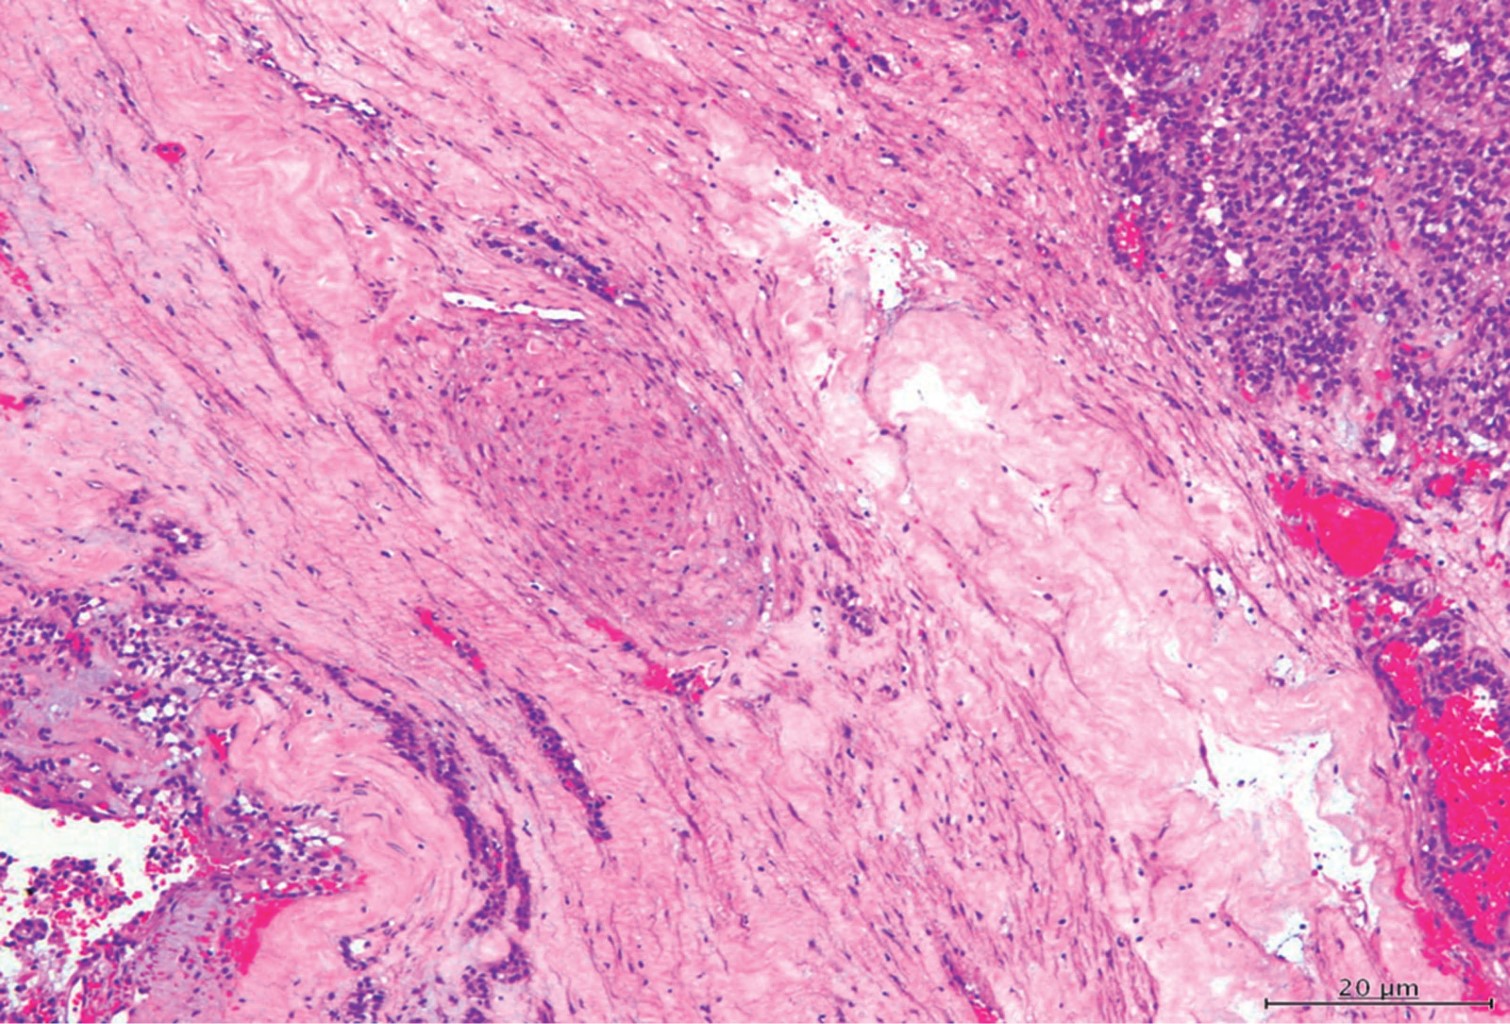

El resultado histopatológico reveló positividad para carcinoma papilar sólido pancreático con ausencia de malignidad en tejidos circundantes como epiplón mayor y ganglio linfático pancreático (Figura 6).

Microscópicamente son células uniformes de apariencia epiteloide, redondas u ovales, con núcleo central y cromatina fina sin actividad mitótica, el estroma es finamente vascularizado y se reconocen cristales de colesterol, histiocitos y calcificaciones;4,5,7 el informe de nuestro estudio microscópico apoyó el diagnóstico de un carcinoma sólido papilar con presencia de embolias vasculares, compromiso perineural, presencia de calcificaciones dispersas y cambios quísticos degenerativos que necesitaron además técnica de inmunohistoquímica para corroborar el diagnóstico.

Para diferenciarlos pueden ser de gran ayuda los métodos de inmunohistoquímica, los que se realizaron en nuestra paciente fueron: pancitoqueratina, la cual dio negativo en células neoplásicas, enolasa positivo débil en células neoplásicas, cromogranina negativa en células neoplásicas, HMB45 negativo en células neoplásicas, KI67 con índice de proliferación celular menor de 1%. Estos tumores también presentan negatividad a marcadores endocrinos y marcadores neoplásicos como el CEA y el CA 19.9;7-9 en nuestra paciente no hubo evidencia de alteración en los mismos.

Figura 6